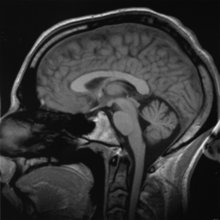

Una investigación abre la puerta a un tratamiento menos agresivo de los tumores encefálicos 03/10/2012Una nueva investigación realizada en la Universidad de Medicina de Viena (Austria) ha permitido caracterizar por primera vez y con gran precisión la respuesta inmunológica del encéfalo frente a la infiltración metastásica en los tumores encefálicos. Este gran avance podría sentar las bases para el desarrollo de nuevas opciones de tratamiento menos agresivas. Los científicos han descubierto que las metástasis en el encéfalo se encuentran con un «muro» de fagocitos, pero que éstos son demasiado débiles para detener el desarrollo del tumor si no cuentan con refuerzos. Para ello es necesario que se movilice un mayor número de glóbulos blancos (linfocitos) como segunda línea defensiva del sistema inmunitario. A raíz de este descubrimiento, los investigadores opinan que podrían desarrollarse nuevas estrategias terapéuticas destinadas a activar en mayor medida los linfocitos u otras partes del sistema inmunitario. Esto se podría hacer mediante medicamentos específicos tales como vacunas o tratamientos con anticuerpos. En la Universidad de Medicina reciben tratamiento cada año para metástasis encefálicas entre trescientos y cuatrocientos pacientes. El tratamiento habitual es la radioterapia aplicada sobre la cabeza o la irradiación generalizada del encéfalo, opciones que llevan aparejados ciertos riesgos y posibles efectos secundarios. Para ciertos tipos de cáncer sólo se dispone de métodos basados en tratamientos farmacológicos en casos excepcionales. Más información CORDIS